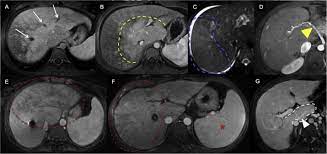

Chiasmata -mə-tə or chiasmas also chiasms 1. Esophageal varices are extremely dilated sub-mucosal veins in the lower third of the esophagus. Located in metro Denver northern Colorado and western Nebraska serving all of the Front Range our team consists of board-certified and fellowship-trained interventional radiologists. This results in hepatic congestion similar to Budd-Chiari syndrome and post-sinusoidal portal hypertension. The patients condition should be monitored throughout the procedure. They are most often a consequence of portal hypertension commonly due to cirrhosis. Toxic injury to liver sinusoids causes sloughing of endothelial cells that embolize to hepatic venules and cause eventual fibrosis of the venules. Coin in the Esophagus. There is no clear consensus regarding the number of occluded veins some authors claim that there should be at least one occluded hepatic vein 7 others state that there are no significant.

Carcinoma of the Colon. Budd-Chiari syndrome a blockage in one or more veins that carry blood from the liver back to the heart. And coumarin skin necrosis adrenal gland hemorrhage and infarction. Toxic injury to liver sinusoids causes sloughing of endothelial cells that embolize to hepatic venules and cause eventual fibrosis of the venules. Chiari malformation CM is a structural defect in the cerebellum characterized by a downward displacement of one or both cerebellar tonsils through the foramen magnum the opening at the base of the skull. Embolism and thrombosis of. La présence dune ou plusieurs affections prothrombotiques est fréquente La prise en charge repose sur un traitement anticoagulant précoce le traitement de l.